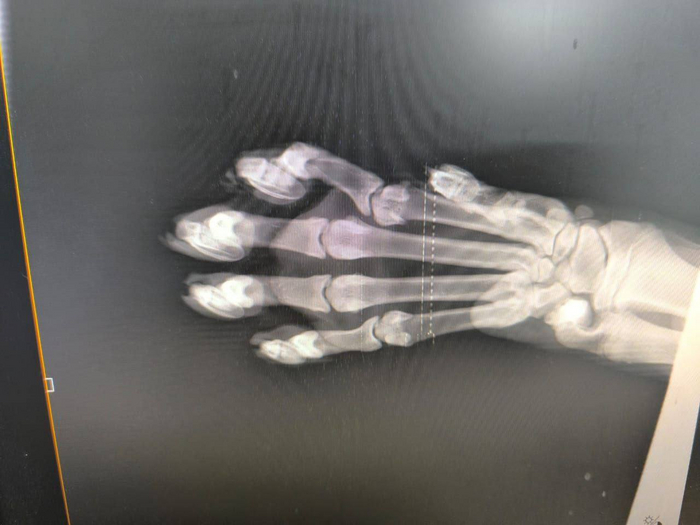

Ветеринарные врачи центра реабилитации осмотрели амурскую тигрицу, отловленную на окраине Дальнереченска (Приморский край).

Примерный возраст полтора года, вес 74 кг. Вес — единственное, над чем надо поработать. Других травм у животного нет. Пока что она остаётся под надзором специалистов МРОО «Центр «Тигр».